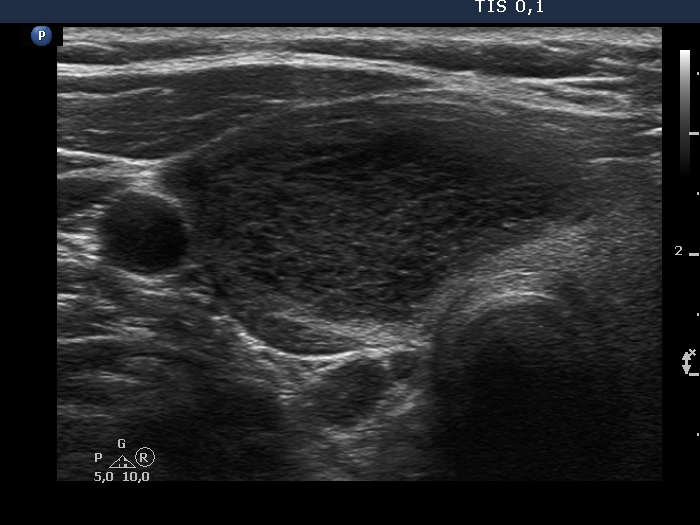

Second examination 3 years later (second, fourth and sixth rows of images):

Ultrasonography. Compared with the previous examination, both the number and the size of discrete lesions in the thyroid have increased.